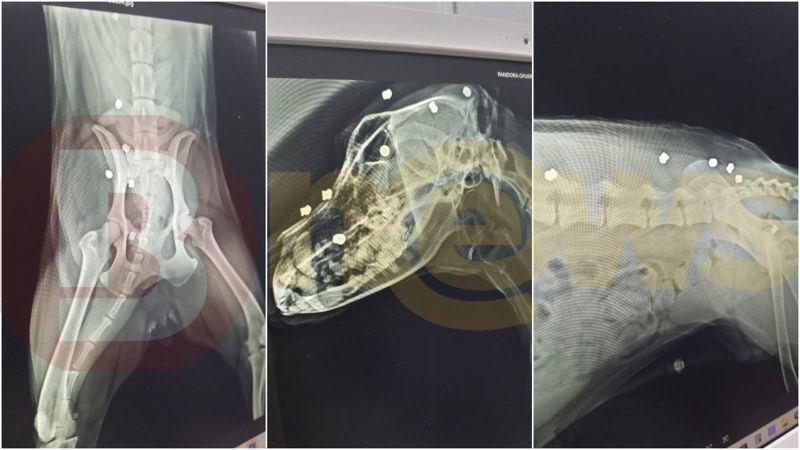

Segundo relatos de vizinhos feitos à reportagem, o morador identificado apenas como Marcones teria atirado 17 vezes com uma espingarda de ar comprimido contra o cachorro de um vizinho após uma discussão. O animal havia fugido da área onde vive e entrou no terreno do suspeito. Outro relato afirma que o agressor atirou no animal mesmo sem qualquer ameaça.

O tutor do animal registrou boletim de ocorrência e está tomando providências legais. A Polícia Civil foi acionada e investiga o caso. Apesar dos disparos, o cachorro sobreviveu.